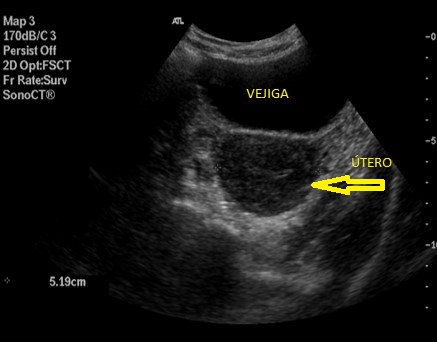

El útero es un órgano hueco. Está constituido por una capa muscular o miometrio y otra capa mucosa o endometrio.

Está situado entre la vejiga Anteriormente y el colon recto sigmoideo posteriormente.

1. Posición global. Puede ser importante hacia donde se inclina el útero; anteroversión y retroversión.